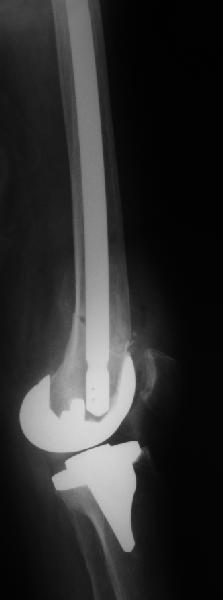

Оперирована по поводу перипротезного перелома н/з бедренной кости Оперирована по поводу перипротезного перелома н/з бедренной кости в ноябре 2010г.Диагноз:закрытый оскольчатый перелом бедренной кости в н/3 со смещением отломков, состояний после эндопротезирования коленного сустава от 2009г.Операция:артропластика коленного сустава, остеосинтез бедренной кости пластиной с угловой стабильностью.В июле операция по поводу несросшегося перелома н/3 бедренной кости,перелом пластины:взятие костного аутотрансплантата из гребня подвздошной кости, удаление пластины, костная аутопластика, остеосинтез бедренной кости пластиной с угловой стабильностью.На контрольном снимке от октября 2012г.- несросшийся перелом бедренной кости, ложный сустав.Что еще можно предпринять? Существуют ли методы лечения, кроме операционных? Поможет ли в данном случае гравитационная терапия7 Или ждать когда все-таки произойдет сращение или еще раз сломается пластина?И произойдет ли сращение вообще? Помогите советом.

Надо удалять пластину и либо вновь синтезировать пластиной, либо делать остеосинтез внутрикостным стержнем. Мы предпочли бы второй вариант. Стержень лучше вводить сверху. Запереть получается очень надежно. В отличие от пластины. стержень можно динамизировать, то есть за счет введения винта вверху в овальное отверстие можно оставить возможность для сближения фрагментов.

Добрый день. Оперировать не рекомендовали. После 3-х лет после операции- вот такая картина. Прокомментируйте пожалуйста снимки.

Снимок только в одной проекции, для более полной оценки ситуации надо и фас увидеть. И в первую очередь узнать о клиническом статусе - жалобы, ось, длина, амплитуда движений в колене, опоросопособность, потребность в дополнительной опоре?

В предыдущем сообщении к сожалению не удалось прикрепипь все снимки.Сейчас это исправляю.Высылаю все снимки в хронологии.

Жалобы следующие:

1.дискомфорт в области крепления пластины ( нужно найти определенное положение, иначе ощущается боль), 2.укорочения конечности в общем не ощущается,

3.колено в суставе полностью не сгибается, но котрактура была еще и до операции по эндопротезированию сустава, сгибалось только на 90 град. После перелома сгибается еще меньше.( Ну это уже не самая большая проблема по сравнению с несрастанием),

4.Хожу с дополнительной опорой на трость, полной нагрузки не даю, т.к. опасаюсь повторного перелома пластины.

По-поводу "оперировать не рекомендовали", имела ввиду своих лечащих врачей, говорили, что гарантии никакой дать не могут на сращение перелома."Ходишь и ходи" Будут проблемы - будем дальше думать.

Прошу Вас прокомментировать динамику. Почему пластина опустилась? И наблюдается ли все-таки сращение?